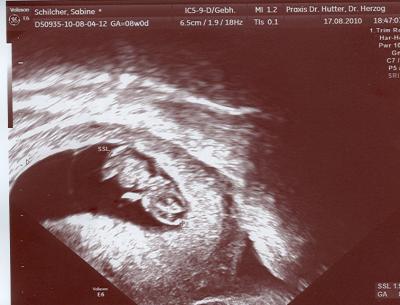

komme grad von Doc und es ist alles super. Krümel ist schon fast 2 cm groß und munter!

Sehr süßes Bild.

Toll! Lauter gute Nachrichten heute! Mensch, das Foto ist ja toll! Auf meinem Foto von gestern sieht man bloß eine große "Bohne", obwohl ich schon 10. Woche bin!

so ähnlich sah mein US-Bildchen in der 9.SSW auch aus und war auch 2cm groß

jetzt ist mein zwerg schon über 4cm groß

... süßes Bildchen, macht grad winke,winke oder? Schön das alles in Ordnung ist. Weiter so! LG, Manu.